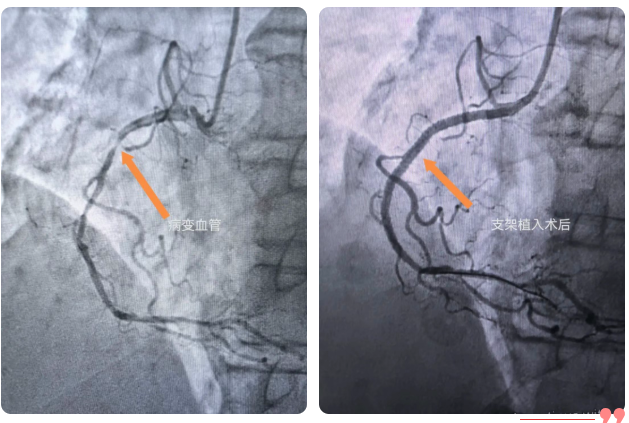

心血管造影+支架植入术齐发力

冠脉造影术通过手腕或者大腿仅2毫米的微创穿刺,导入导管直至心脏冠状动脉。高清数字减影血管造影(DSA)设备实时生产血管三维影像,精准定位狭窄部位、程度与范围,为治疗提供“导航级”依据。而冠脉支架植入术是对确诊的严重狭窄(狭窄程度≥70%)或急性心梗患者,植入合金网状支架,撑开堵塞血管,恢复血流,治疗“立竿见影”。手术全程局部麻醉、患者清醒,耗时短,恢复快。万医心内科已全面开展心血管造影+支架植入术,双管齐下,解决您的“心”困扰。